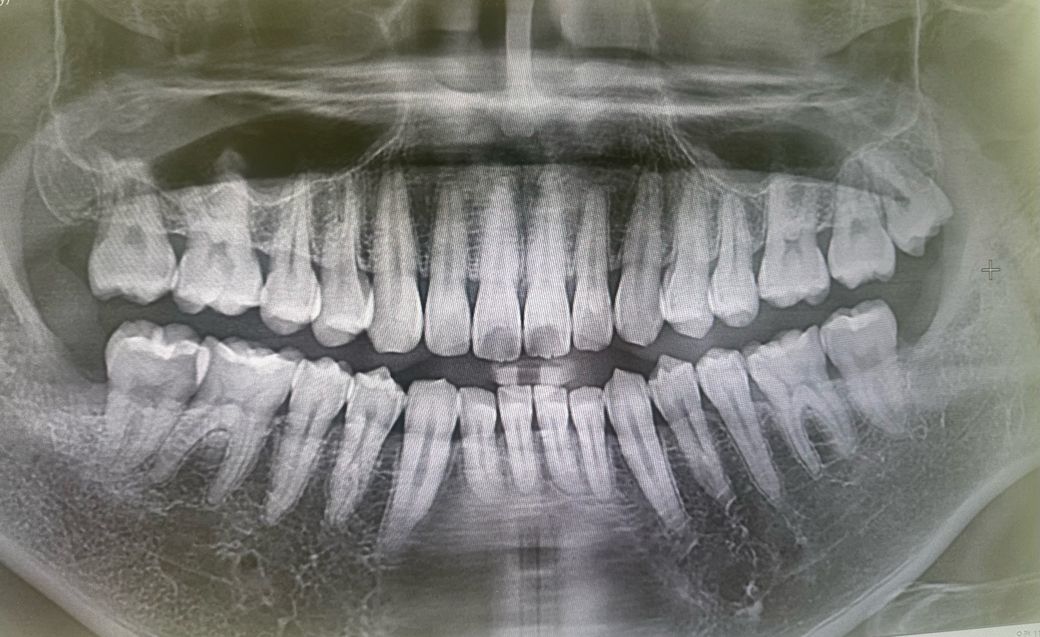

차례대로 사랑니발치전, 발치후, 가까이서 찍은 엑스레이입니다…

• 3번 째 사진

해당 부위는 잇몸 하방 치조골에 근접한 충치로 치료가 쉽지 않습니다. 더군다나 원심측이라 기구 접근이 어려워 치료를 시작한다면 크라운을 씌워주어야 하고, 잇몸을 째고 치조골 높이를 낮추어야 합니다.

일단은 사랑니 발치를 하고나서 다시 확인을 해보셔야될것같습니다. 파노라마 상으로는 충치가 있어 보입니다.